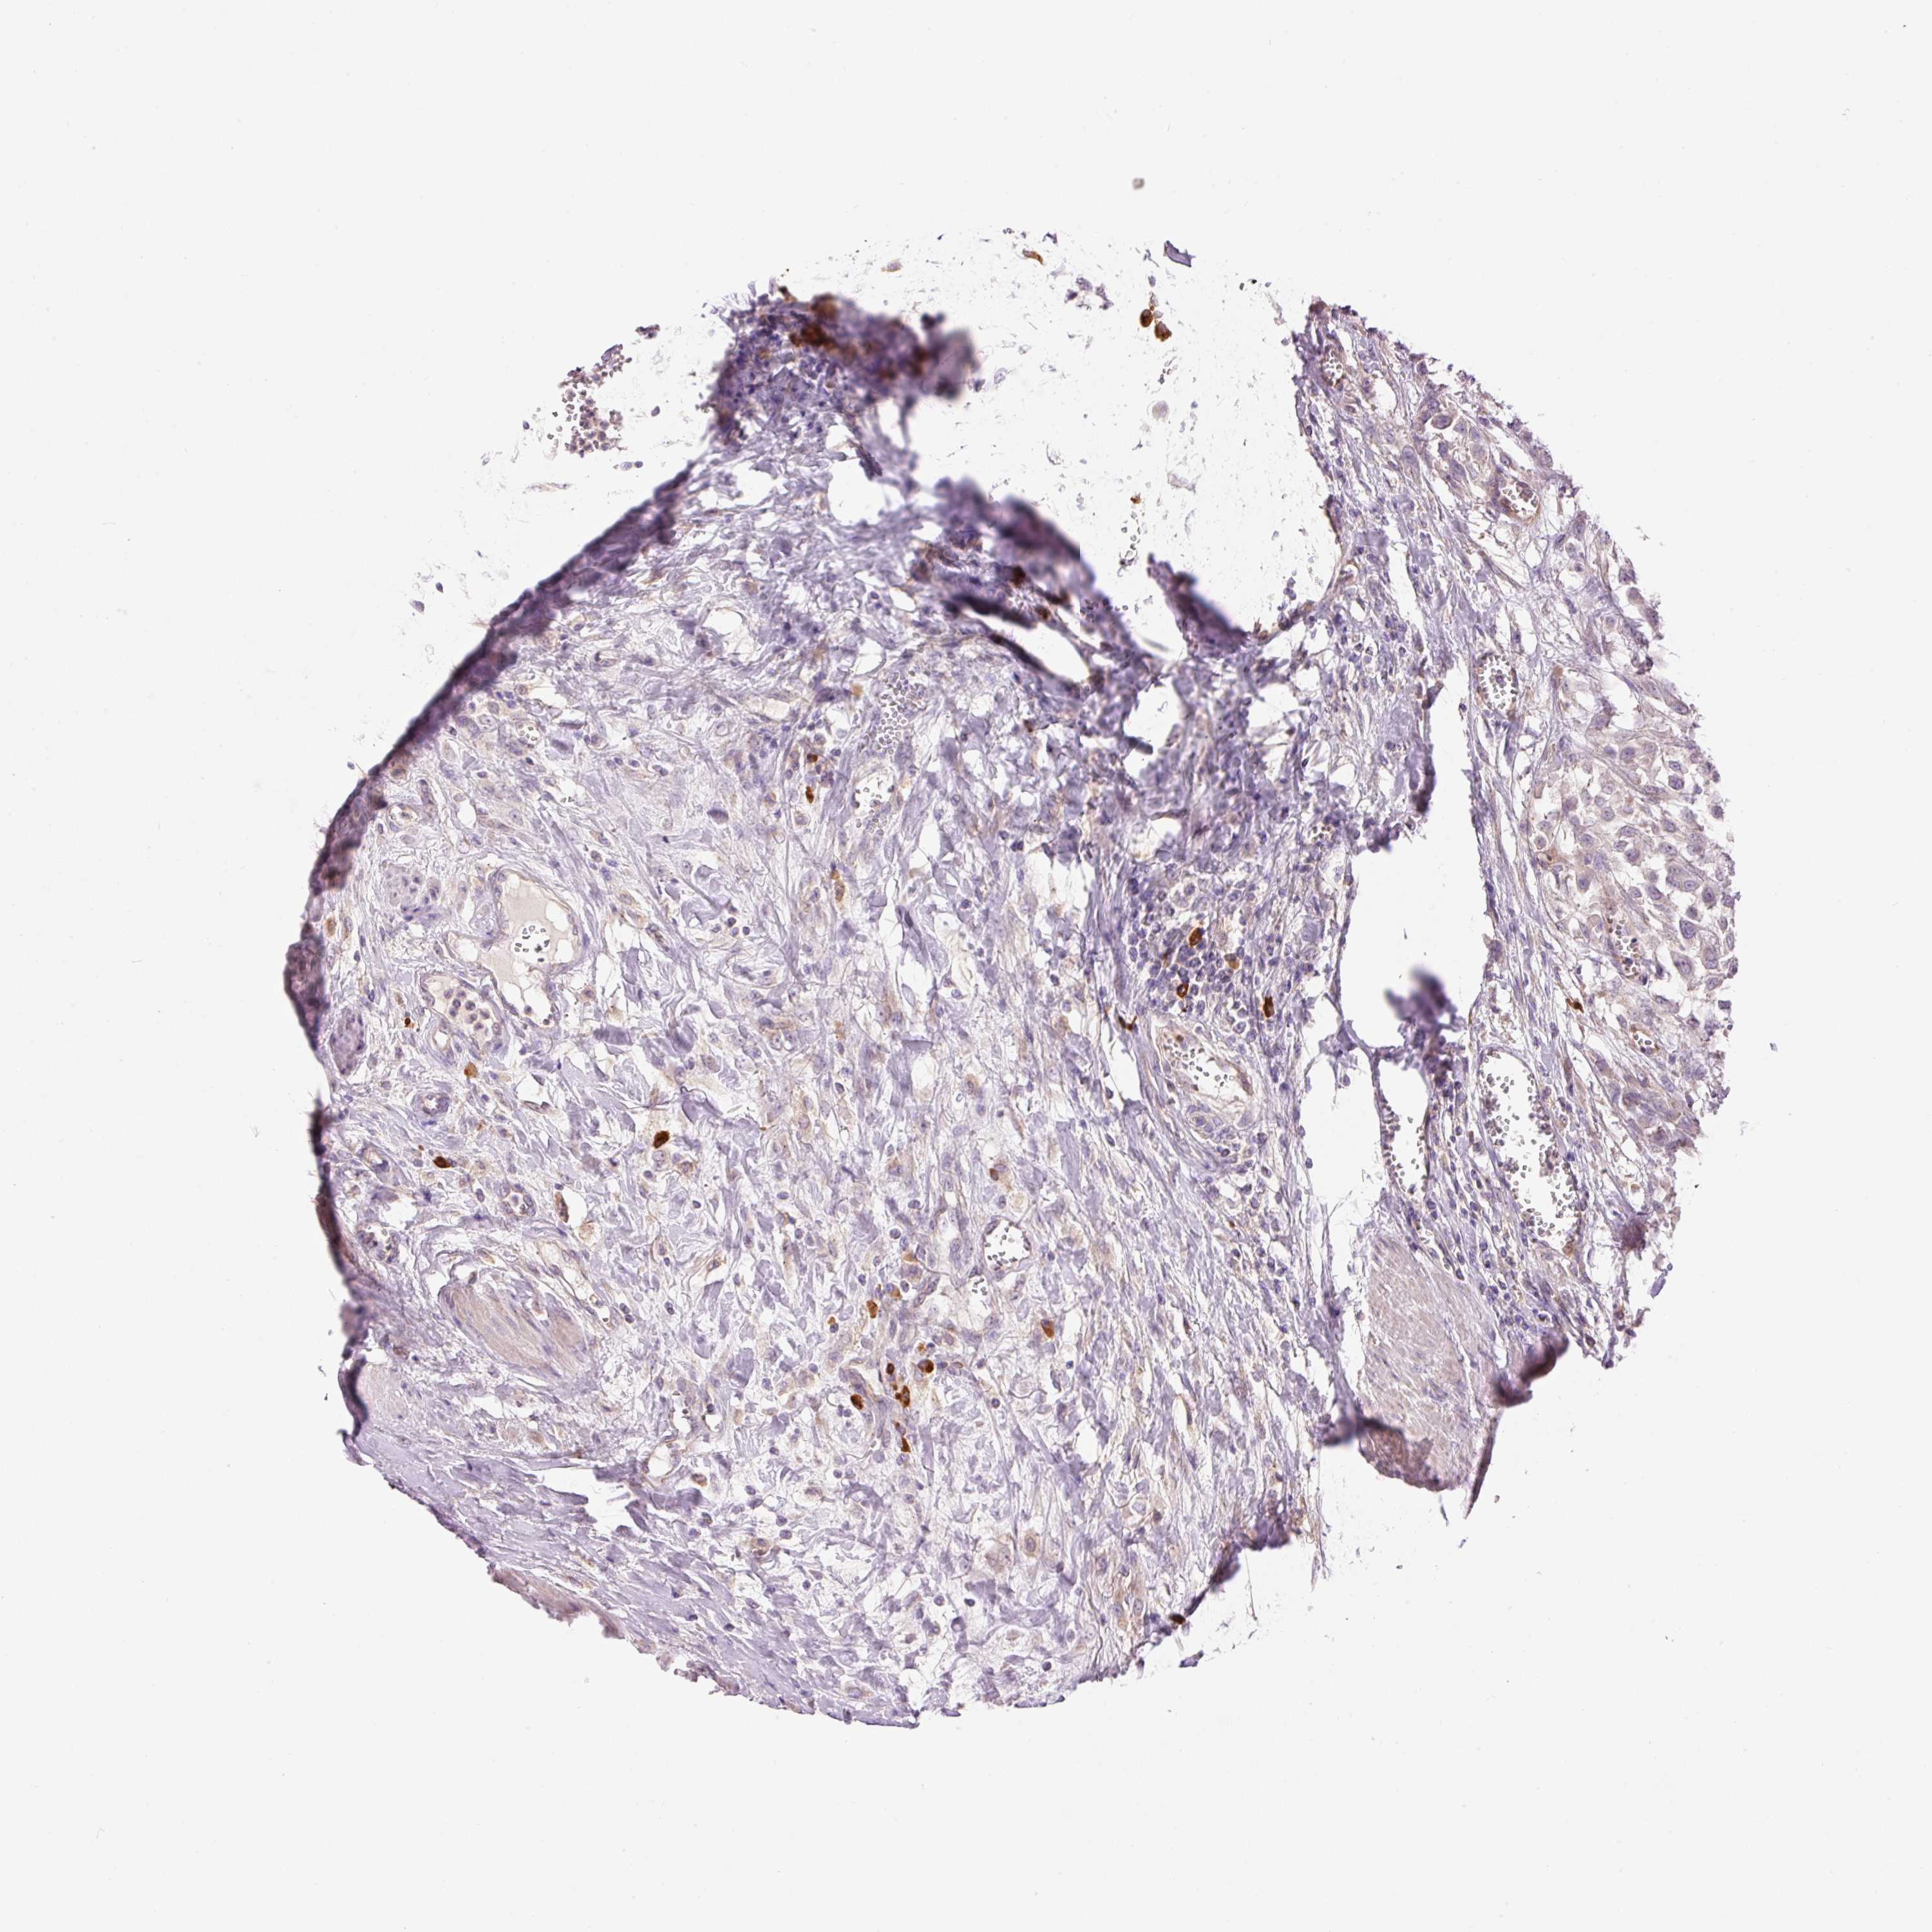

UROTHELIAL CANCER - Protein expressioni

A mouse-over function shows sample information and annotation data. Click on an image to view it in a full screen mode. Samples can be filtered based on level of antibody staining by selecting one or several of the following categories: high, medium, low and not detected. The assay and annotation is described here.

Antibody stainingi

Antibody staining in the annotated cell types in the current human tissue is reported as not detected, low, medium, or high, based on conventional immunohistochemistry profiling in selected tissues. This score is based on the combination of the staining intensity and fraction of stained cells.

Each image is clickable and will lead to virtual microscopy that enables deeper exploration of all samples and also displays staining intensity scores, fraction scores and subcellular localization as well as patient and tissue information for each sample.

Antibody HPA050409

Antibody HPA054211

Urothelial carcinoma, Low grade

Urothelial carcinoma, High grade

Urothelial carcinoma, NOS